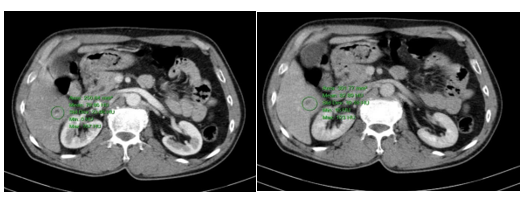

– Chụp CT ổ bụng: Nốt vôi hóa gan phải đường kính 5mm, gan có vài nang, đường kính lớn nhất 9mm.

Hình ảnh nang nhỏ gan và nốt vôi hóa gan phải( vòng tròn màu xanh).